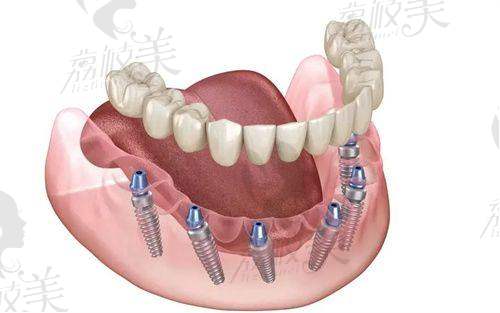

—— 全口/半口无牙颌方案:面对骨量不足患者,他可以灵活制定方案,实现稳固自然修复。

—— 数字化美学修复与咬合重建:让人工牙“不落俗套”,功能与美观两全齐美。

张俊伟医生不仅会“种牙”,更擅长“算牙”。他积极推广数字化种植技术,将传统经验与高端影像技术融合,种植过程效率高且精细,真正做到“种得稳、种得久、种得美”。他还是“技耗分离”理念的倡导者,强调医生技术和种植系统的各司其职,这不仅给患者带来合理的费用结构,也提高了整体治疗质量。